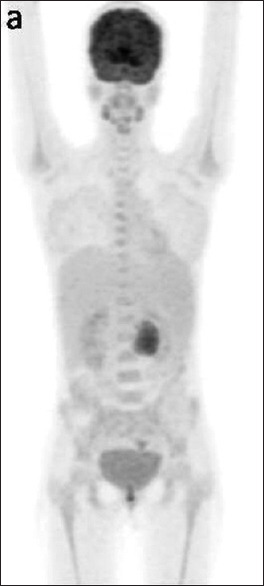

Castleman disease is a nonmalignant, lymphoproliferative disorder. Unicentric disease type involves a single enlarged lymph node or nodal regions, and multicentric disease involves multiple lymph node site involvement. We present a case of 26-year-old young female presented to outpatient with complaint of generalized weakness and abdominal pain for last 2 months. Her imaging included positron emission computed tomography which showed soft-tissue mass along the body of pancreas. Endoscopic ultrasound done showed nodal mass with extensive calcification and doppler endoscopic ultrasound showing arborising vessels. Fine needle aspiration cytology (FNAC) and biopsy taken showed lymphoid cells and diffuse hyaline material. After suboptimal response to chemotherapy regimen, she underwent open laparotomy and excision of the retroperitoneal mass.

Castleman病是一种非恶性淋巴增生性疾病。单中心性疾病类型涉及单个肿大的淋巴结或淋巴结区域,多中心性疾病涉及多个淋巴结部位。我们报告了一例26岁的年轻女性,在过去的两个月里,因全身无力和腹痛而门诊就诊。她的成像包括正电子发射计算机断层扫描,显示胰腺体部的软组织肿块。内窥镜超声检查显示结节性肿块伴广泛钙化,多普勒内窥镜超声波检查显示树枝状血管。细针抽吸细胞学检查(FNAC)和活检显示淋巴细胞和弥漫性透明质。在对化疗方案反应不佳后,她接受了剖腹手术和腹膜后肿块切除术。